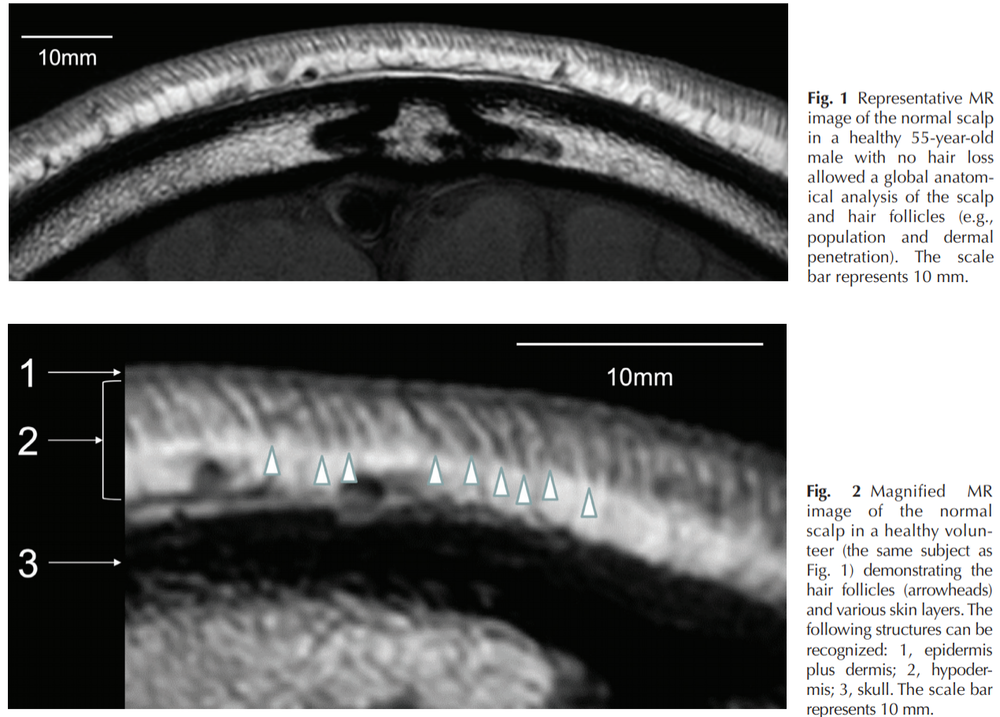

retinoic acid promotes bone profileration at the expense of cartilage(and fats).that crap destroys cartilage, induces autoantigen-homing on the hair follicle outer rooth sheath(and cartilage in the joints)- and is upregulated in balding scalps. ALso, the balding scalp has been shown to be excessively thin when compared to normal hairy scalps in MRI scans.

View attachment 147038

my analysis of this- is that bony layer, the skull(the dark matter in the MRI scan)- replaces the connective tissue above it- n that is loose cartilage. SHH ups SOX(- master regulator chondrogenesis http://genesdev.cshlp.org/content/16/21/2813.full and all things cartilage amd is a direct target of SHH.